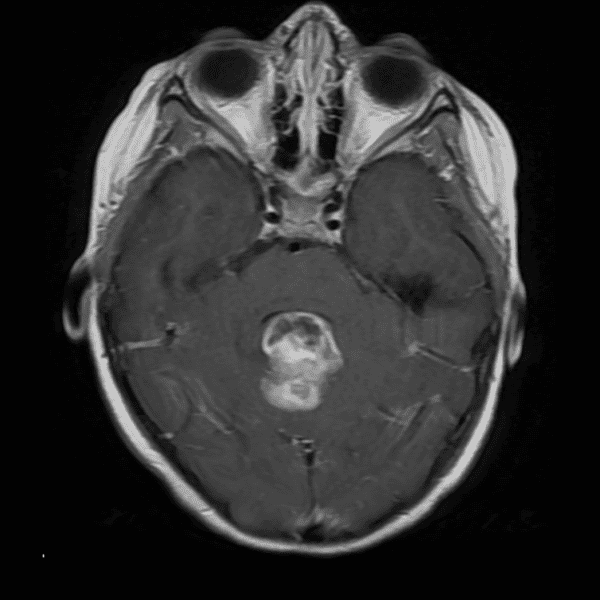

Classic Cases